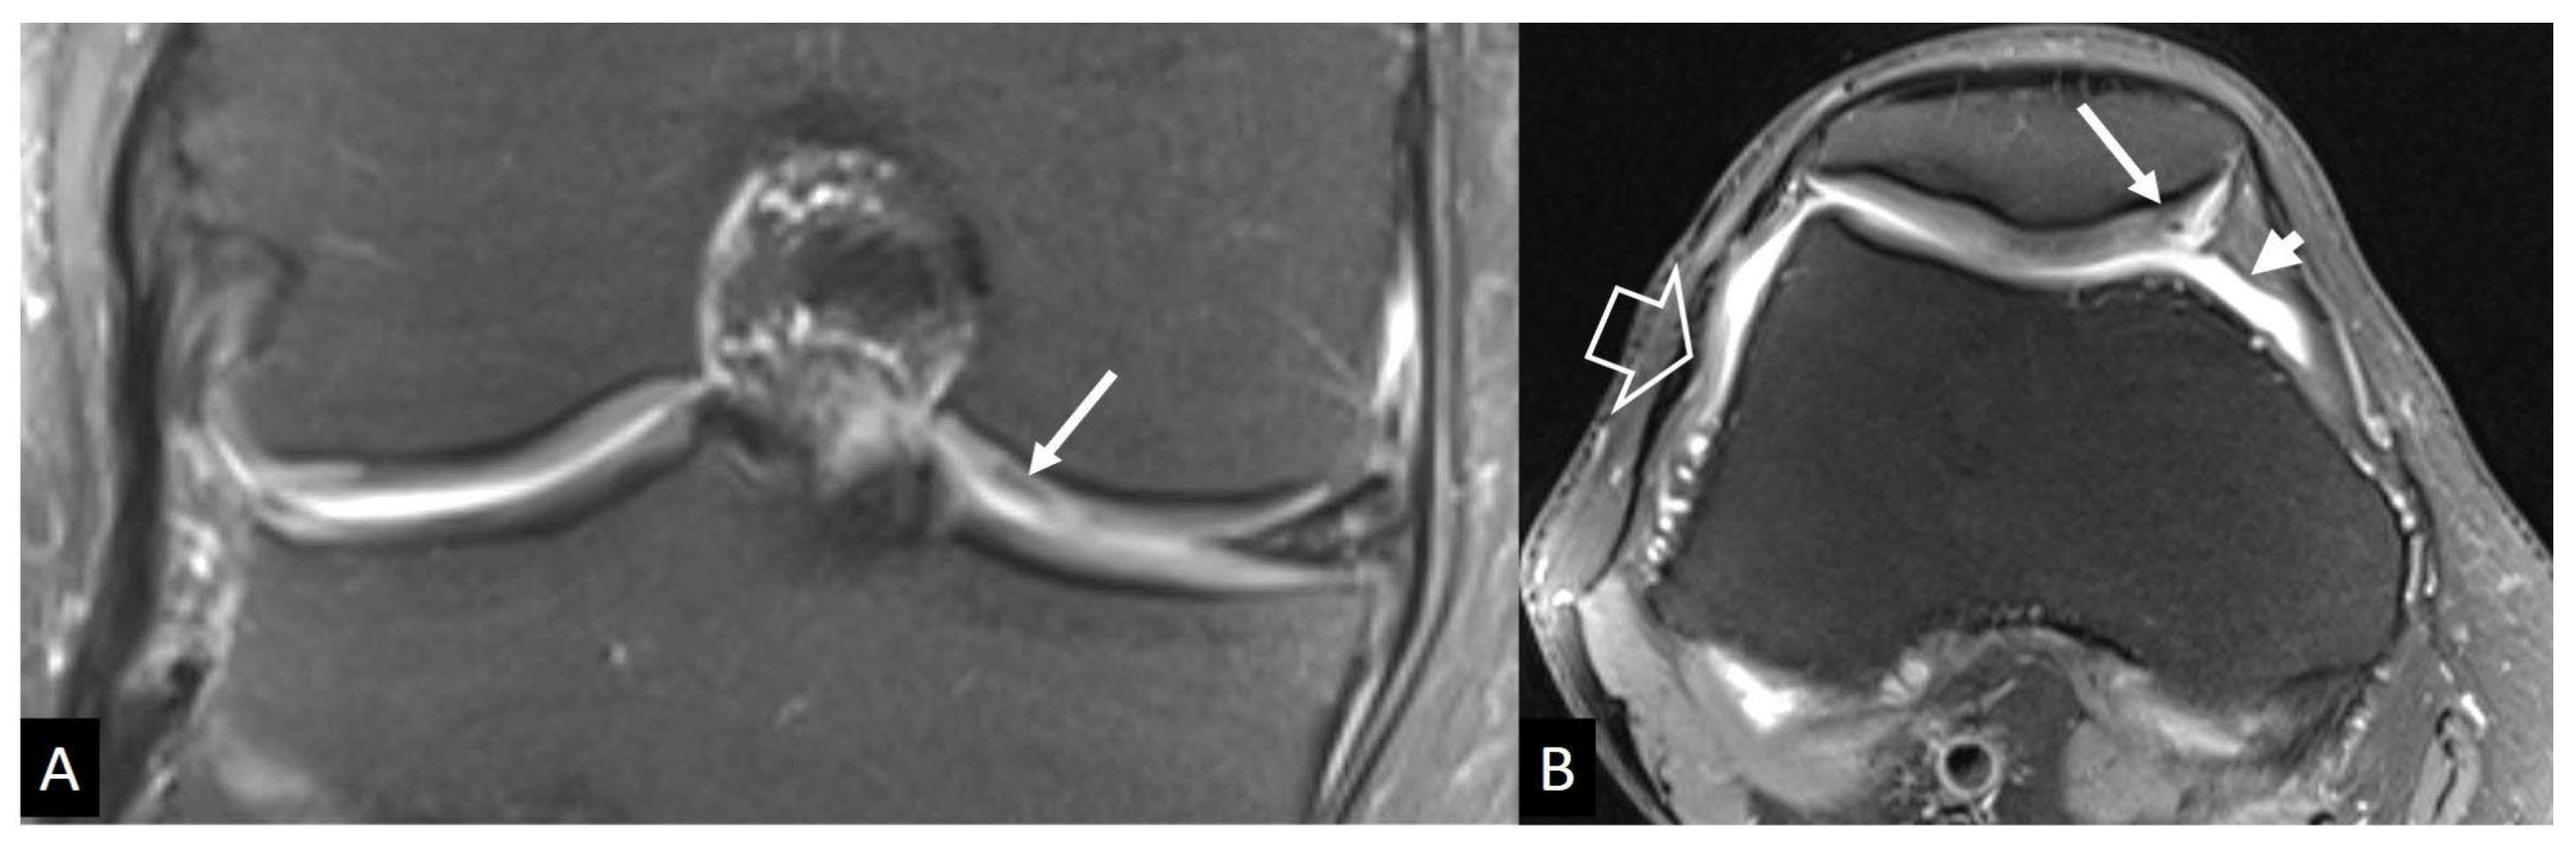

3. b.ii. Neuropathic Arthropathy

3. b.iii Crystal-Induced Arthropathies